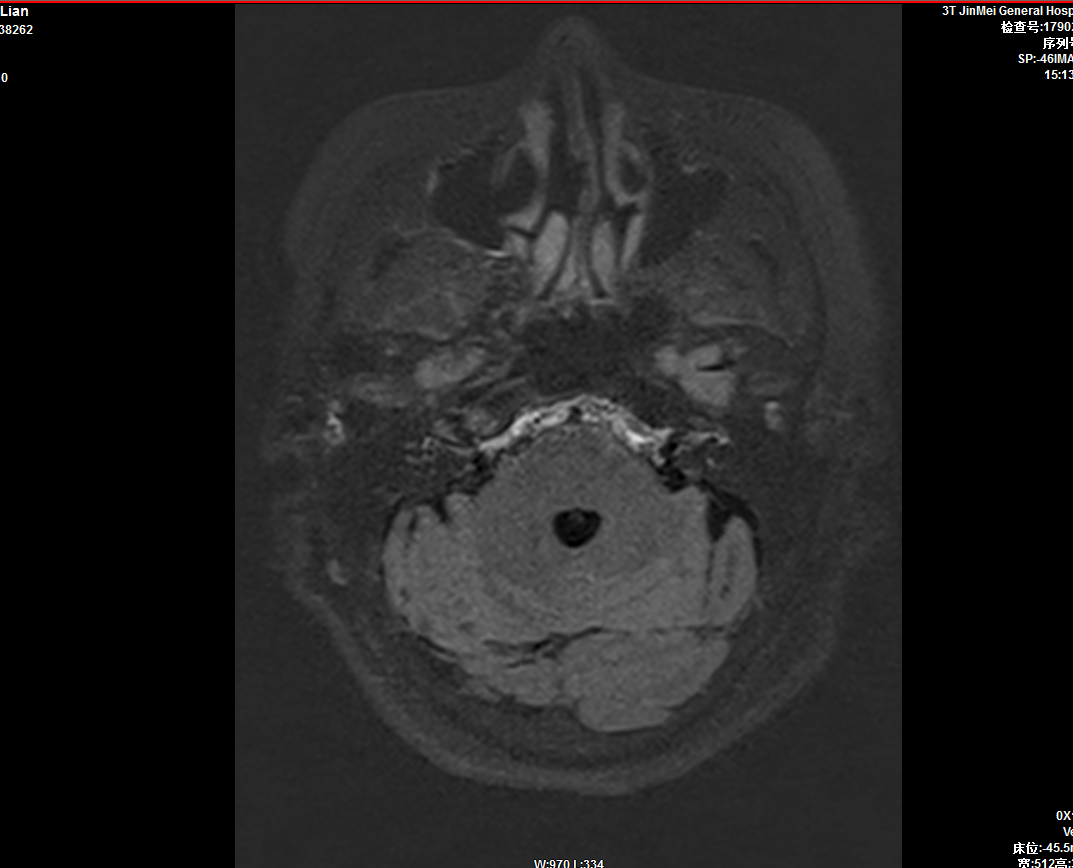

2、惡性腫瘤的術(shù)前TNM分期;

3、MRI的功能成像評(píng)價(jià)超急性期腦梗死,指導(dǎo)臨床治療;CTP、PWI成像評(píng)價(jià)腦缺血性病變、腫瘤性病變;CTA、MRA評(píng)價(jià)顱內(nèi)外血管性病變。

頭顱灌注成像ASL